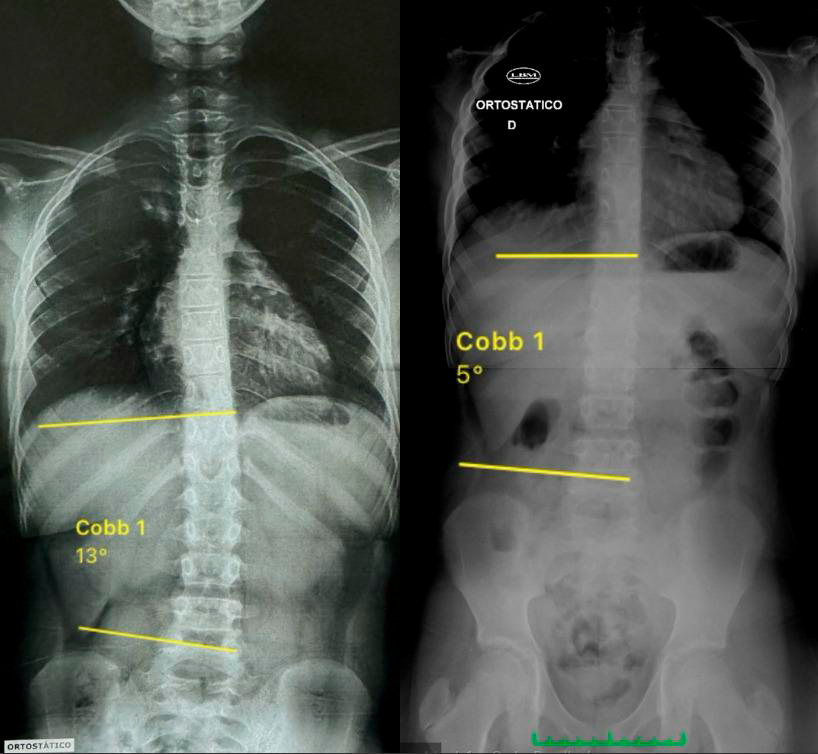

Para ilustrar a eficácia desta abordagem, vamos apresentar um caso clínico de sucesso, onde um paciente jovem conseguiu reduzir significativamente a curvatura da escoliose através de um programa estruturado de exercícios específicos.

Resultado do Tratamento

O paciente iniciou o tratamento com uma escoliose de 13 graus. Após 3 meses, a curvatura reduziu para 5 graus. Além disso, houve uma melhora significativa nas curvas fisiológicas de cifose e lordose. Como a escoliose é clinicamente significativa apenas acima de 10 graus, o paciente agora está livre de escoliose e de complicações futuras, graças ao diagnóstico precoce e ao tratamento adequado.